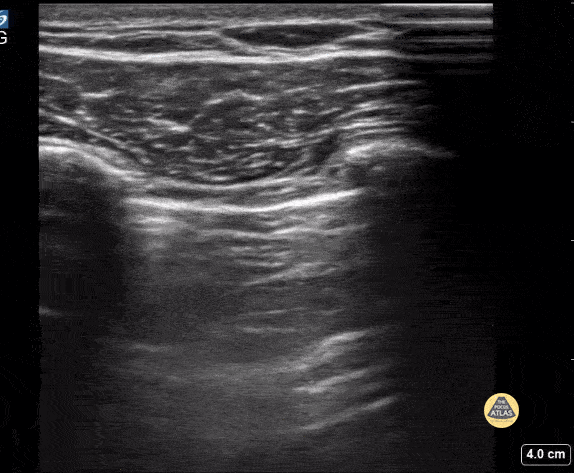

Peds-Lung - No Lung Sliding

Pt presented with shortness of breath of sudden onset. Found to have absence of lung sliding consistent with a large pneumothorax that required chest tube placement. Contributor: Kathryn Pade, MD, Rady Children's Hospital San Diego